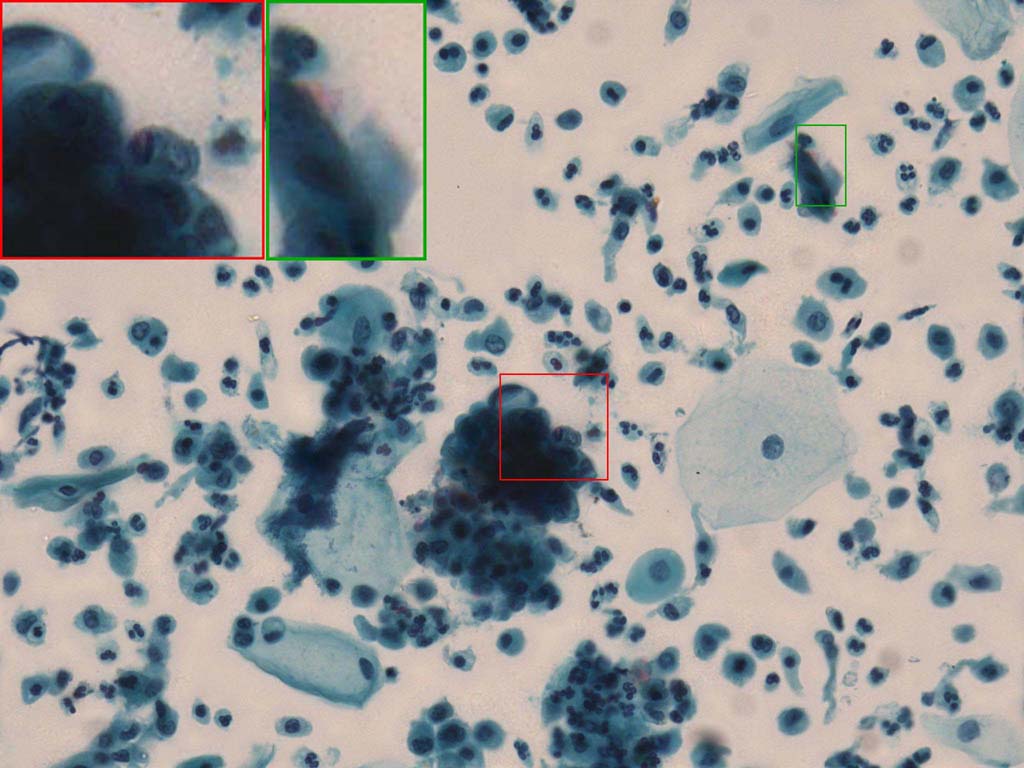

To demonstrate the effectiveness and efficiency of the proposed image fusion method , we conduct a set of comparative experiments on three image datasets. The first is composed by 8 pairs of multi-modal medical images and the second one contains 15 pairs of multi-focus gray or color natural images. These two datasets are often used in many related papers and some examples are shown in Figure 3(a) and Figure 3(b). The third one is a new multi-focus cervical cell image dataset collected by ourselves, which consists of 15 groups of color images and each group contains a series of multi-focus cervix cell images with size of or , etc. Some source examples are shown in Figure 3(c). Our source code implemented in C++ along with the new multi-focus cervical cell image dataset is available online.

Figure 9, Figure 10 and Figure 11 show the comparative fused results of the multi-focus cell images shown in Figure 3(c). For clarity, we also present a closeup view in the right-bottom of each sub-picture in Figure 9 and Figure 10. As shown in the close-up views of Figure 9, the fused images based on DSIFT, IM, MWGF and BF methods are extremely blurred in the boundary and fail to keep the details of cell nucleus. Furthermore, the DTCWT and NSCT based methods produce halo artifacts in the fused images, while GFF and CNN based methods fail to preserve the small cell nucleus. LP-SR based method nearly works fine which keeps the most of the details of the small size cells, but the integrity of the clustered large size cells is damaged. Fortunately, in our proposed method, the integrity of the clustered large size cells is preserved and most of the isolated small size cells are maintained from the original images, which demonstrates the best visual quality.

Similarly, as shown in the close-up views of Figure 10, the fused images from DSIFT, IM, MWGF and BF are blurred and lose some nucleus details, while the results from DTCWT, GFF, CNN and NSCT produce halo artifacts. LP-SR based method can keep details well but also produces halo artifacts and other noise. Our method can preserve the focused areas of different source images well without introducing any artifacts. For the example illustrated in Figure 11, the fused images generated by DSIFT, DTCWT, IM and NSCT all fail to preserve the focused areas of different source images and result in extremely blurred images. The GFF, CNN, MWGF and BF based method introduces a lot of color distortion of the nucleus regions and the obvious halo artifact. The result of LP-SR based method is close to the one of our method but introduces some odd color distortion. Again, our method produces fused image which can preserve the focused areas of different source images well without introducing any artifacts.